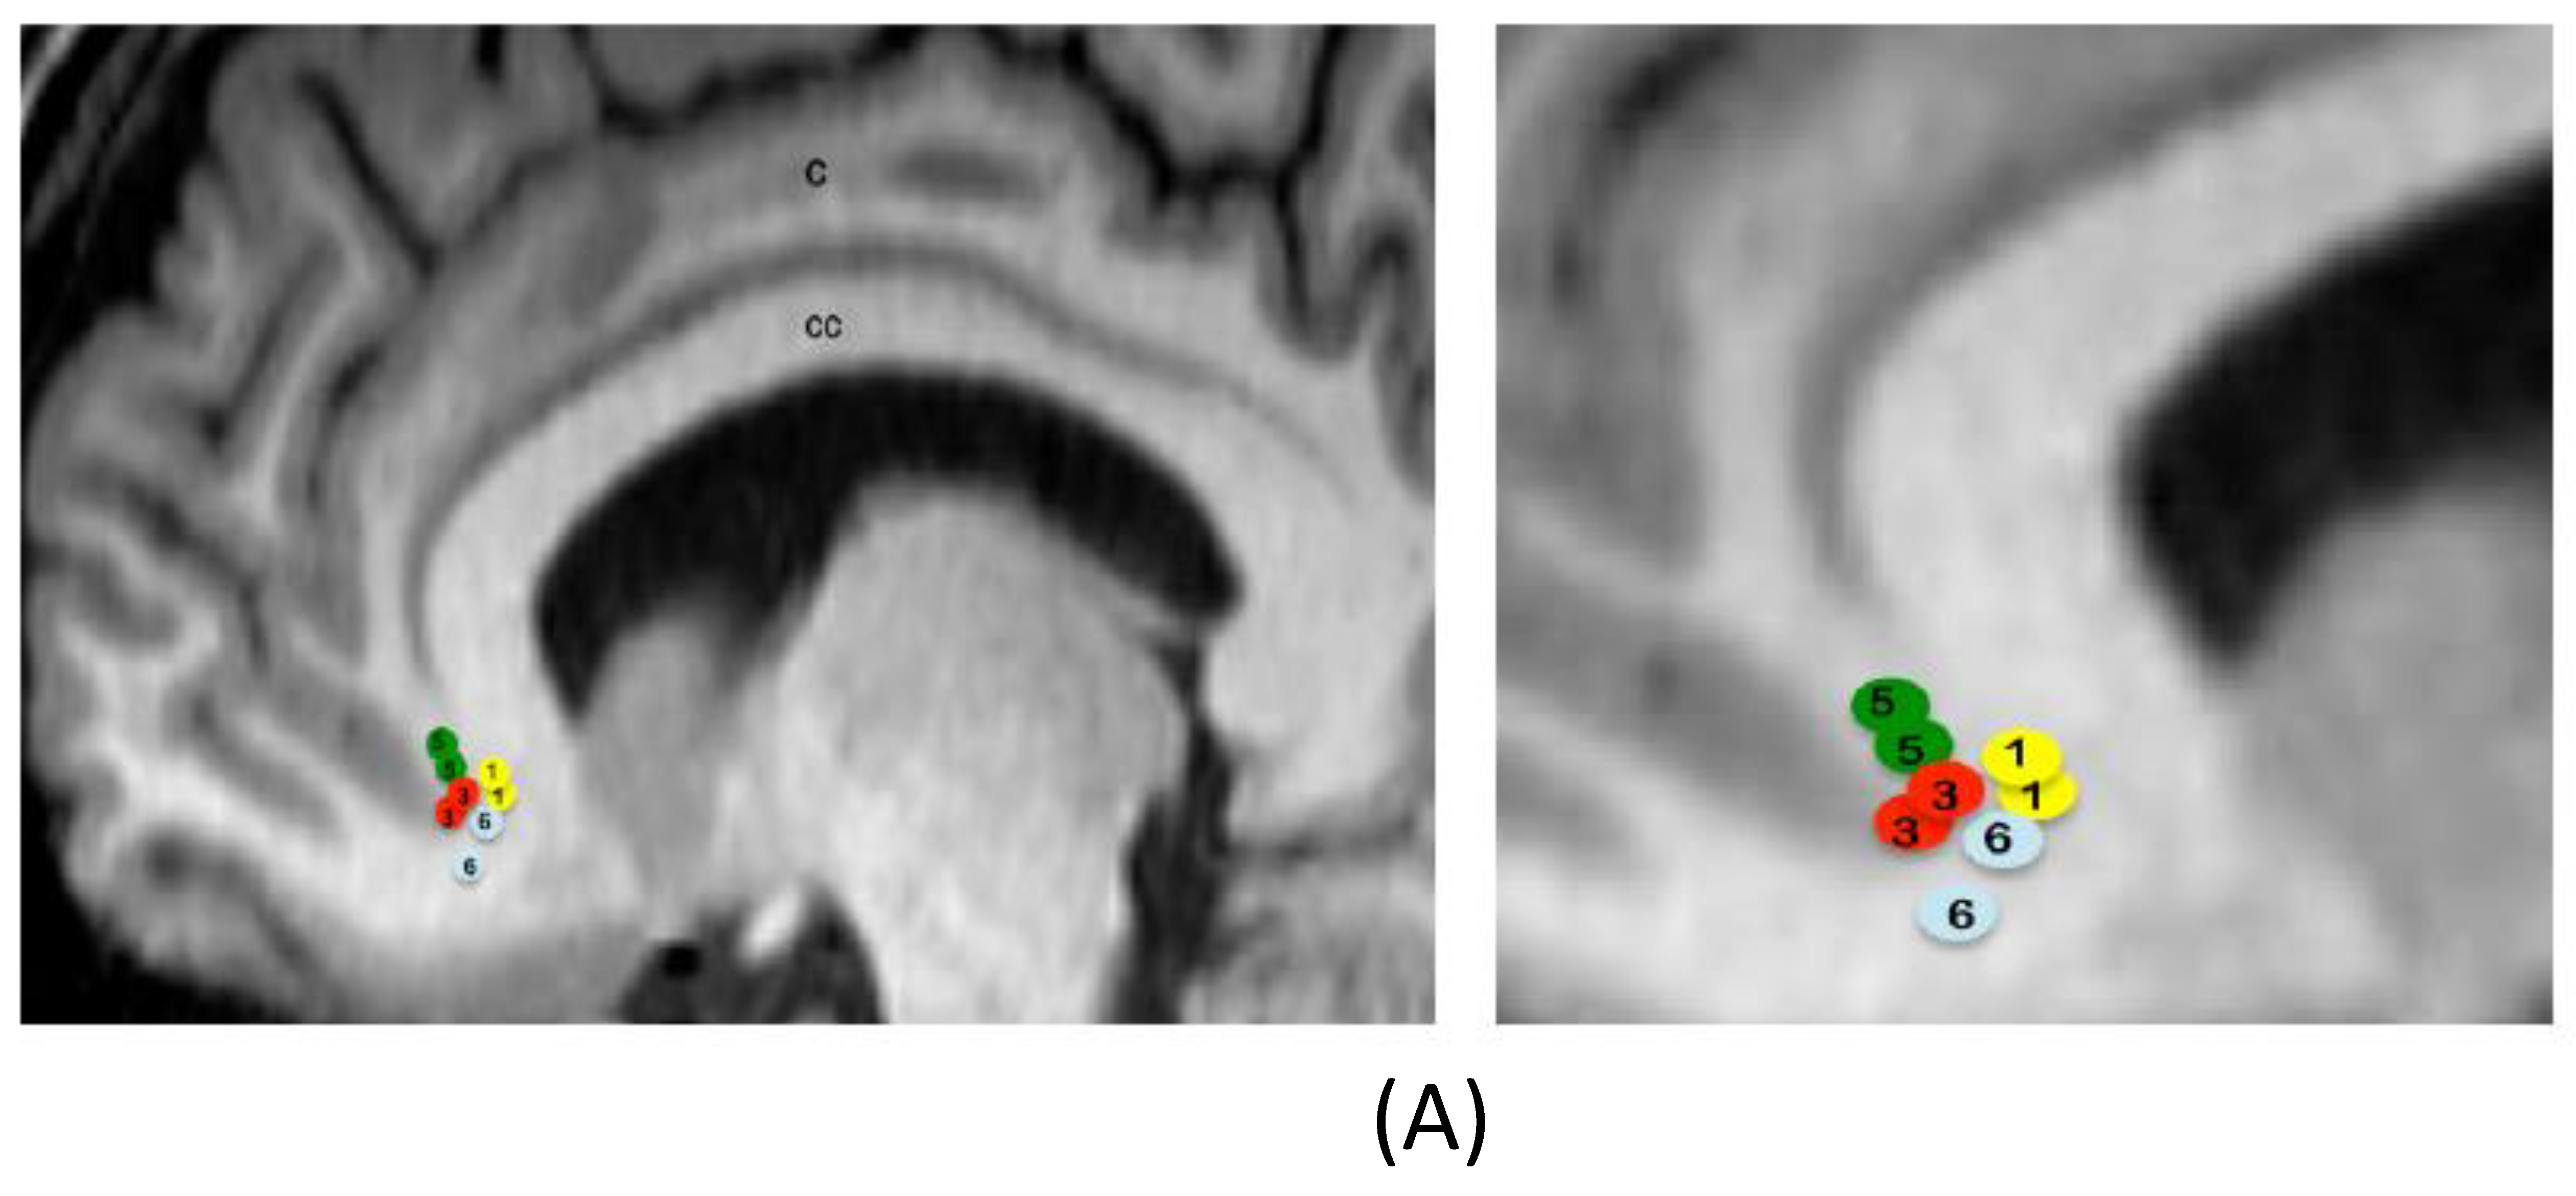

Table 1 describes the demographic and clinical characteristics of the sample, with the active contacts and stimulation parameters. Figure 2 shows location of electrode active contacts.

Figure 2. Location of electrode active contacts. (A) Location of electrode contacts on a sagittal view for patients with DBS on the subcallosal cingulate. Circles are schematic representations of electrode active contacts. Numbers within circles correspond to each patient. The figure at the right side is an enlargement. C = cingulate. CC = corpus callosum. (B) Location of electrode contacts on a coronal view for patients with DBS on the nucleus accumbens. Circles are schematic representations of electrode active contacts. Numbers within circles correspond to each patient. The figure at the right side is an enlargement. CA = caudate nucleus. CI = internal capsule. P = putamen. DBS = deep brain stimulation.